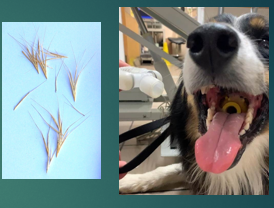

Foreign body

Partial obstruction, e.g Grass seeds can cause inflammation which narrows the airway

Small twigs, apple cores, tennis balls